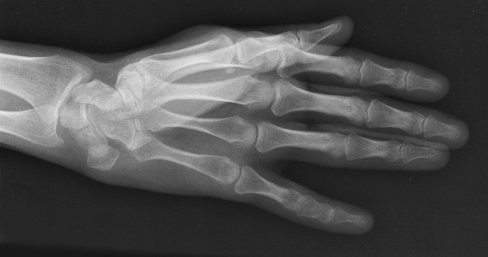

Xray 4

In addition to stretching, my doc prescribed OTC anti-inflammatories and recommended using ice-packs before bed. All of this has helped not only my wrist, but also my street cred. Between the fingerless gloves and icepacks on my hands at night, I’m feeling a lot like a boxer. 🙂

If you’re suffering with work-related pain in your hands or wrists, get professional help.  Talk to your doctor, see a physical therapist, and do your prescribed stretches. You’re an artist and you want to keep creating as long as possible. Take good care of those beautiful hands!